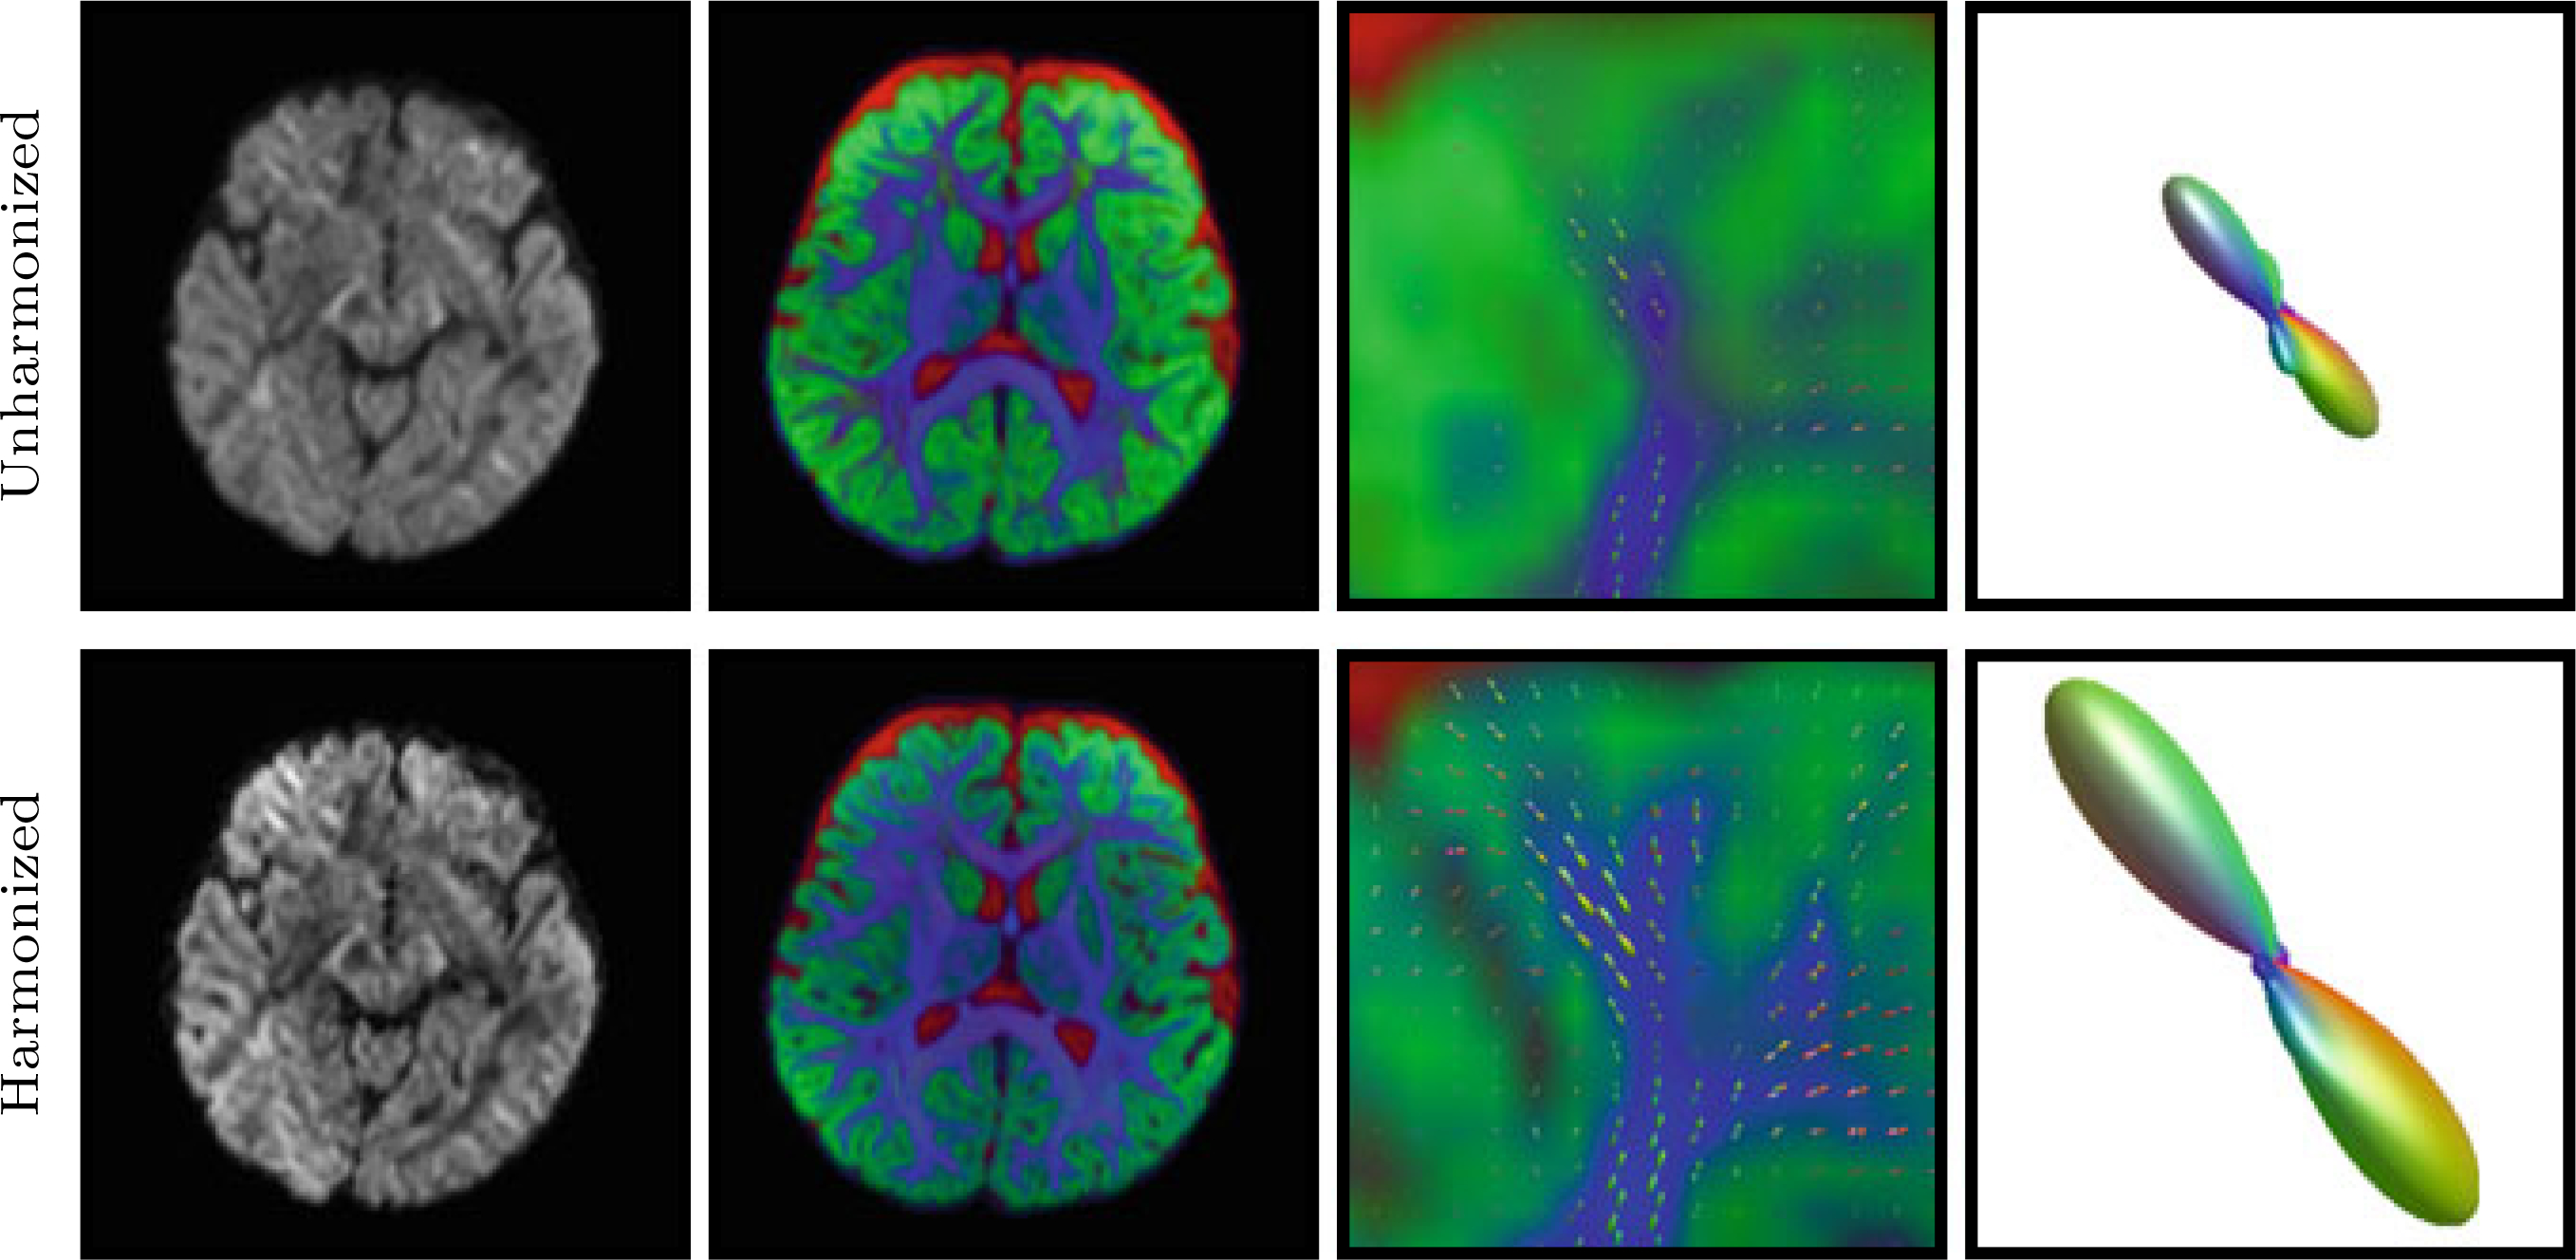

Multi-tissue constrained spherical deconvolution [10] was performed to estimate the fiber ODFs. From Fig. 3, one can appreciate the increase in sharpness of the FODFs after harmonization. The tissue volume fraction map also reveals greater details with further extension into cortical regions.

Fig. 3. Fiber ODFs.

Left to Right: DW image, tissue volume fraction map (Blue: White matter; Green: Gray matter; Red: Cerebrospinal fluid), Close-up view of forceps minor, and an FODF in forceps minor before and after harmonization